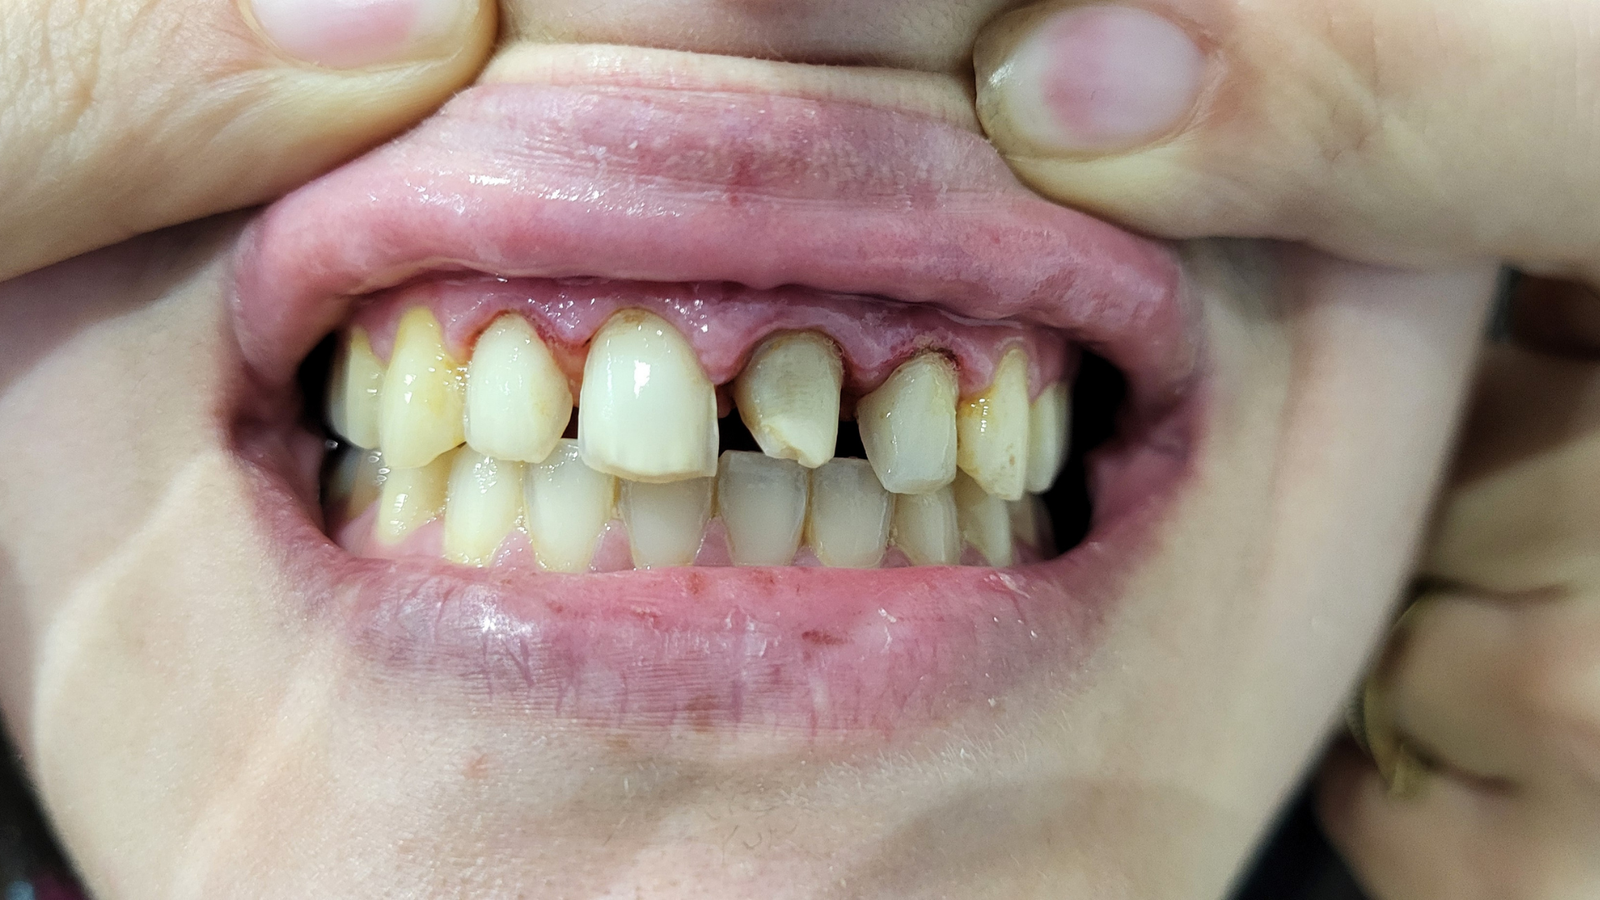

Réhabilitation complète avec mise en charge immédiate (4 implants bas / 6 implants haut)

Le patient se présente avec des dents qui bougent, en haut et en bas.

Nous avons commencé par la mâchoire inférieure avec 4 implants et une mise en charge immédiate.

Trois mois après, le haut a été fait avec le même principe avec 6 implants.

Cette fois-ci, il existait un déficit osseux, résolu par une technique d’expansion sans avoir recours à la greffe d’os.

Les prothèses réalisées sont vissées, ce qui permet de les enlever, les nettoyer une fois par an, ou résoudre n’importe quel problème.